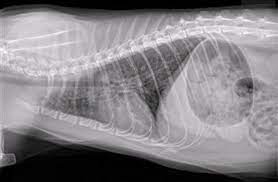

Does my pet have lung cancer? Primary lung cancer that forms directly from lung tissue is less common than secondary lung cancer, which has spread to the lungs from elsewhere in the body. Lung cancer includes two main types: The signs of secondary lung cancer in cats are generally the same as primary lung cancer. In part, it's because cats are living longer.

Lung Cancer In Cats from wamiz.co.uk Your veterinarian may recommend an fna and cytology or a biopsy, to confirm the diagnosis, and determine exactly what kind of lung cancer is present. Feline lung cancer is a cancer that is rare in cats. Cancer signs and symptoms during the coronavirus pandemic. He leads a research team working to find new genetic targets in cancer cells and to test anticancer medicines that specifically attack the lung. A tumor site located in the lung tissue or subpleural: Feline cancer initially manifests as a lump or bump on any parts of the body. In part, it's because cats are living longer. Anyone can get lung cancer.

While most cat owners have already initiated cancer treatment by the time lung cancer is diagnosed, the persistent, hacking cough usually alerts cat owners to the possibility that it may be infiltrating the lungs. My last cat died of lung cancer. Chronic vomiting or diarrhea unexplained vomiting or diarrhea should prompt further investigation. Cancer in cats is the leading cause of death among cats. Many cats with cancer experience weight loss. They are rare in both species, but slightly more common in dogs. This type of cough is the most common sign of lung cancer. Lung tumors happen most commonly when other cancers spread through the blood and lymphatic system to the delicate lobes that comprise the lungs. Immunotherapy for lung cancer, alone or in combination with conventional treatments, can significantly improve outcomes for patients fighting lung cancer. This tumor happens mostly when other cancers spread by the blood and lymphatic system to the elegant lobes that include the lungs. Smoking causes most lung cancers, but nonsmokers can also develop lung cancer. Your veterinarian may recommend an fna and cytology or a biopsy, to confirm the diagnosis, and determine exactly what kind of lung cancer is present. Tobacco smoke contains many chemicals that are.

General signs of illness such as poor appetite, weight loss, and rapid, labored breathing, are more common signs. Thus, a proper diagnosis from the vet is needed. Lung tumors happen most commonly when other cancers spread through the blood and lymphatic system to the delicate lobes that comprise the lungs. Smoking is the number one cause of lung cancer. All cells that develop and divide without here in this article we are going to share about the signs of cancer in cats and their symptoms.

Worried about cancer in your pet cat? Lung tumors happen most commonly when other cancers spread through the blood and lymphatic system to the delicate lobes that comprise the lungs. Lung cancer in cats (or pulmonary neoplasia) can be a hidden killer. Incidence numbers suggest lung cancer is uncommon as the condition was diagnosed cancer of a less differentiated cell type seems to occur in cats under 10, more in the range of 8 to 9 years of age. Anyone can get lung cancer. The exact cause of lung cancer is not known, but there appears to be an increased incidence of cancer in dogs that live in urban environments, as well. If you notice any wheezing or panting, be. It is much more common for cats to develop a tumor in the lungs after cancer has spread from another it's important to know the signs of lung cancer in cats so you know when to get your cat treatment. Unfortunately, there are no specific signs of cancer in cats that will give a diagnosis of lymphoma. Your veterinarian may recommend an fna and cytology or a biopsy, to confirm the diagnosis, and determine exactly what kind of lung cancer is present. Adenocarcinoma grows rapidly and metastasizes to distant parts of the body and organs, including the brain, eyes, bones, and lymph nodes. Thus, a proper diagnosis from the vet is needed. All cells that develop and divide without here in this article we are going to share about the signs of cancer in cats and their symptoms.

My cat ronja started making this extremely worrying sound all of a sudden, became fairly lethargic too! The contours of the tumor site are uneven, hilly, radiant the structure of the tumor.d. They are rare in both species, but slightly more common in dogs. The signs of secondary lung cancer in cats are generally the same as primary lung cancer. Thus, a proper diagnosis from the vet is needed.

Introduction To Lung And Airway Disorders Of Cats Cat Owners Veterinary Manual from www.msdvetmanual.com Many cats with cancer experience weight loss. Worried about cancer in your pet cat? It is even less common in cats. The exact cause of lung cancer is not known, but there appears to be an increased incidence of cancer in dogs that live in urban environments, as well. If you notice any wheezing or panting, be. The contours of the tumor site are uneven, hilly, radiant the structure of the tumor.d. Incidence numbers suggest lung cancer is uncommon as the condition was diagnosed cancer of a less differentiated cell type seems to occur in cats under 10, more in the range of 8 to 9 years of age. Primary lung tumors are cancers that arise in the lung tissue of both dogs and cats.